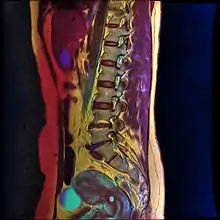

Color MRI showing nabothian cyst as small blue circle in cervical region.

Nabothian cysts are also incidentally found during MRI imaging. During the healing process of chronic cervicitis, squamous epithelium of ectocervix proliferates and enter the cervical canal (endocervix), covering and obstructing the columnar epithelium of endocervical glands. Thus, retention of mucus in the endocervical glands causes cyst formation. The size of the cyst may vary from a few millimetres to 4 cm in diameter.[3]

T1-weighted MRI imaging would show intermediate to high intensity while T2-weighted imaging would show high signal intensity. Findings of solid components separating multiple cysts would be suggestive of adenoma malignum (a form of cervical cancer).[3]